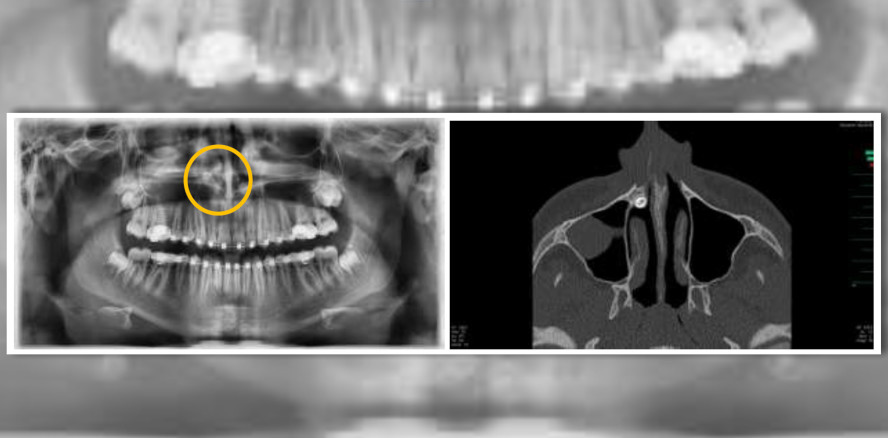

Ein 15-jähriger Patient wurde vom Kieferorthopäden mit einer Verschattung der rechten Kieferhöhle und einer Hyperdontie2 in die Klinik für Mund-, Kiefer- und Gesichtschirurgie des Klinikums Bremen-Mitte überwiesen. Das angefertigte OPT zeigte einen verlagerten, überzähligen Zahn 13a (oberer Eckzahn). Nach Komplettierung der Bildgebung durch eine Computertomographie konnte der Zahn im rechten oberen Nasenboden lokalisiert werden.

Darüber hinaus litt der Patient an einer polypenförmigen Schleimhautschwellung der rechten

Kieferhöhle. In allgemeiner Schmerzausschaltung wurde endoskopisch gestützt eine Infundibulotomie3 mit nachfolgender Kieferhöhlenrevision und Entfernung des Zahnes 13a aus dem rechten Nasenboden über die Nase durchgeführt. Der postoperative Heilungsverlauf war komplikationslos, die definitive Histologie bestätigte die Verdachtsdiagnose einer chronischen Sinusitis maxillaris (Kieferhöhlenentzündung). Der Patient ist nach dem Eingriff beschwerdefrei und mit dem Ergebnis sehr zufrieden.